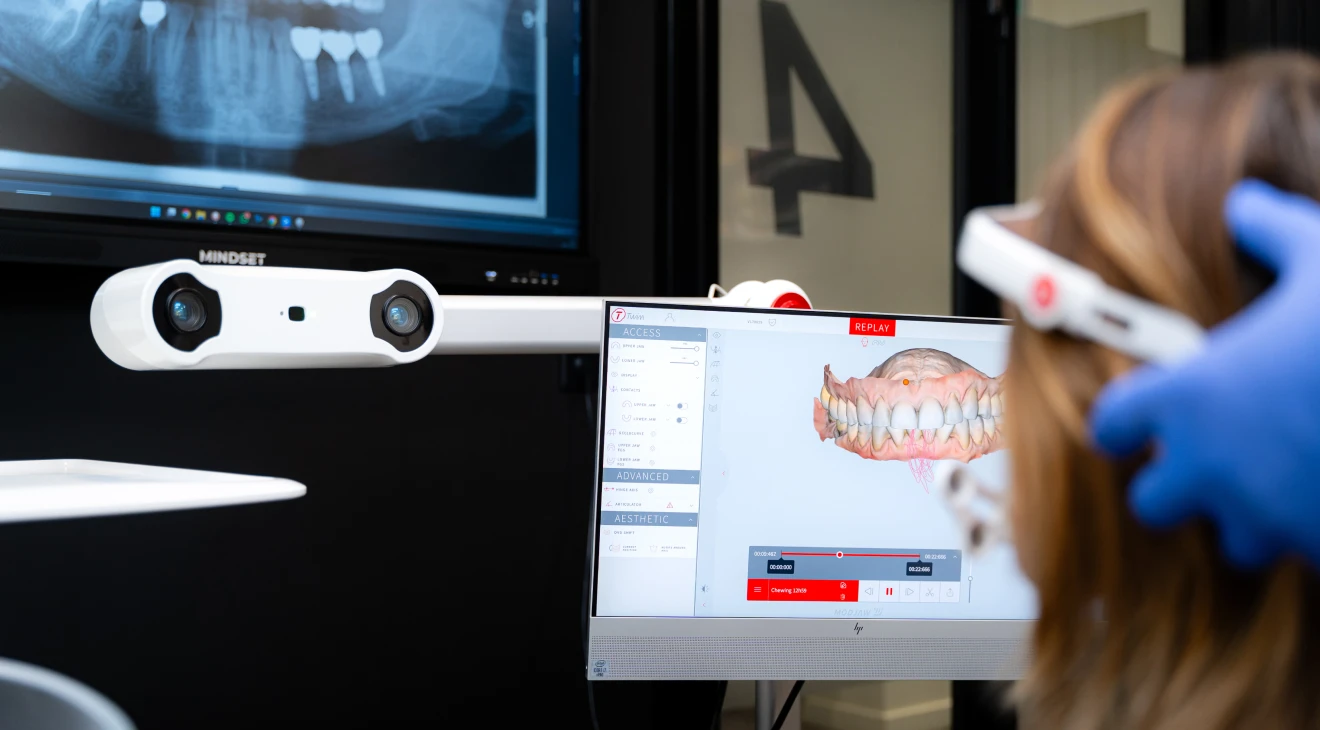

Modjaw (4D)

Grâce à la technologie Modjaw 4D, nous analysons en temps réel les mouvements de votre mâchoire pour un diagnostic d’une précision inégalée. Cette approche dynamique permet d’adapter les soins prothétiques et occlusaux avec une exactitude sur mesure.